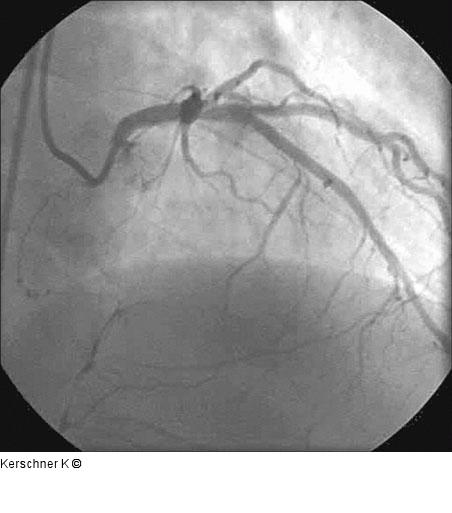

Abbildung 14: Kontrollangiographie Kontrollangiographie nach 3 Monaten - RAO/kranial |

Kontrollangiographie nach 3 Monaten - RAO/kranial |